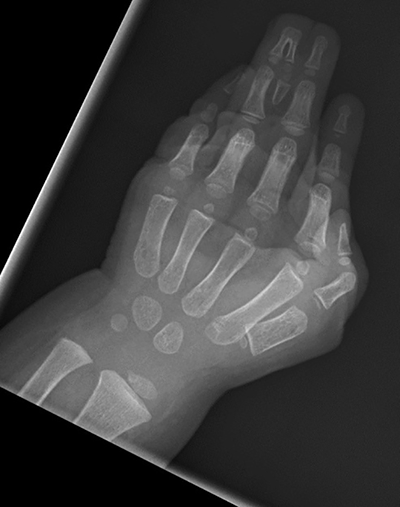

Figure 6. Preop x-ray showing complex complete syndactyly with bony synostosis.